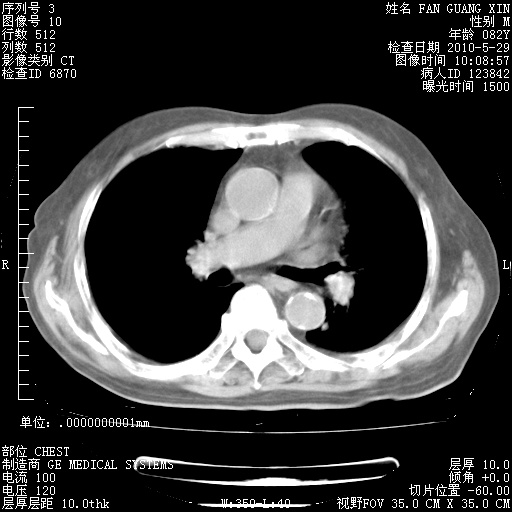

再治疗10天后的肺部CT

再治疗10天后的肺部CT 纵膈窗

阅读此次胸部CT,肺间质渗出性改变较入院时有吸收。目前从体温、白细胞、中性分叶明显增高,肯定存在细菌感染(发生医院感染哦,若无消化道及泌尿系统等感染的依据,肺部感染可能大)。若你院头孢哌酮舒巴坦钠耐药率较高,同意你的方案,若48小时体温仍高,可考虑使用碳青霉稀类抗菌药物,同时可予超声雾化、注意滴数时加大液体量。白蛋白33.30g/L较低哦,需加强营养等支持治疗。